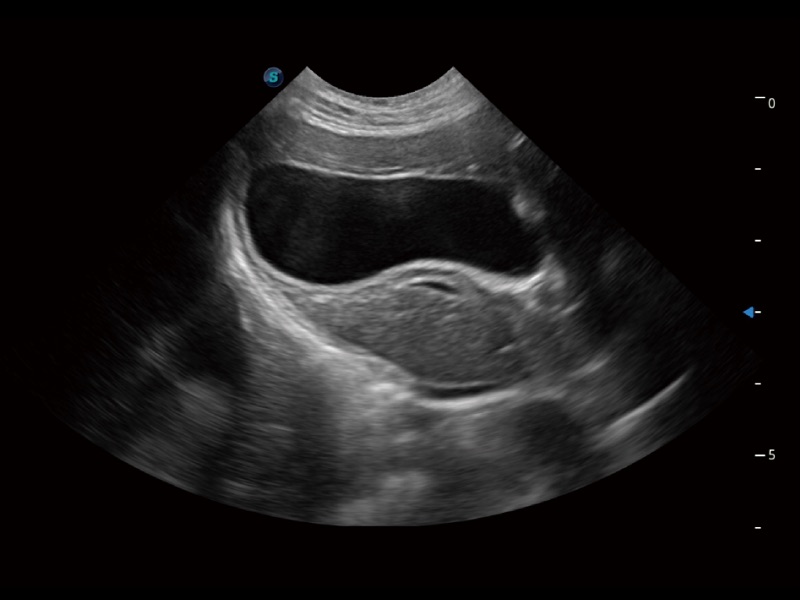

一鍵自動(dòng)識(shí)別膀胱壁及自動(dòng)測(cè)量膀胱容積,不受膀胱形狀和大小的限制,幫助醫(yī)生快速精準(zhǔn)獲得測(cè)量的數(shù)據(jù)。